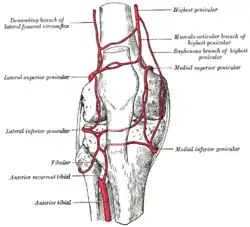

Blood supply

The femoral artery and the popliteal artery help form the arterial network or plexus, surrounding the knee joint. There are six main branches: two superior genicular arteries, two inferior genicular arteries, the descending genicular artery and the recurrent branch of anterior tibial artery.[24]

The medial genicular arteries penetrate the knee joint.